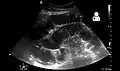

Small bowel obstruction on ultrasound[19]

Radiological signs of bowel obstruction include bowel distension (small bowel loops dilated >3 cm) and the presence of multiple (more than 2) air-fluid levels on supine and erect abdominal radiographs.[16] Ultrasounds may be as useful as CT scanning to make the diagnosis.[17]